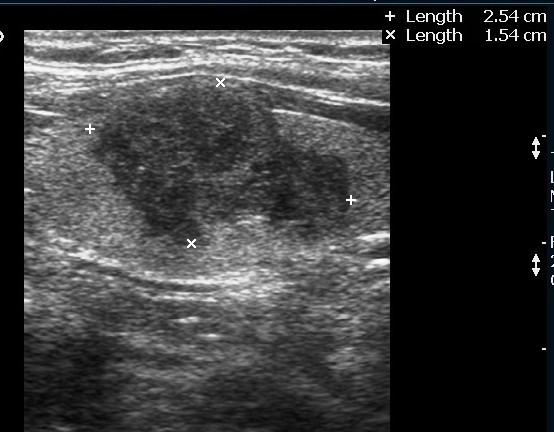

Case 2 : Thyroid Malignancy

A 27 year female complained of swelling in left side neck and it notably increased over a period of 6 months.

Ultrasound Images:

Ultrasound features of a malignant thyroid nodule : solid, hypoechoic irregular margins, absence of a hypoechoic halo around the nodule.

Hypoechoic lesions have a higher risk of being malignant. Lymphadenopathy and local invasion of adjacent structures are highly specific features of thyroid malignancy but are less commonly seen.